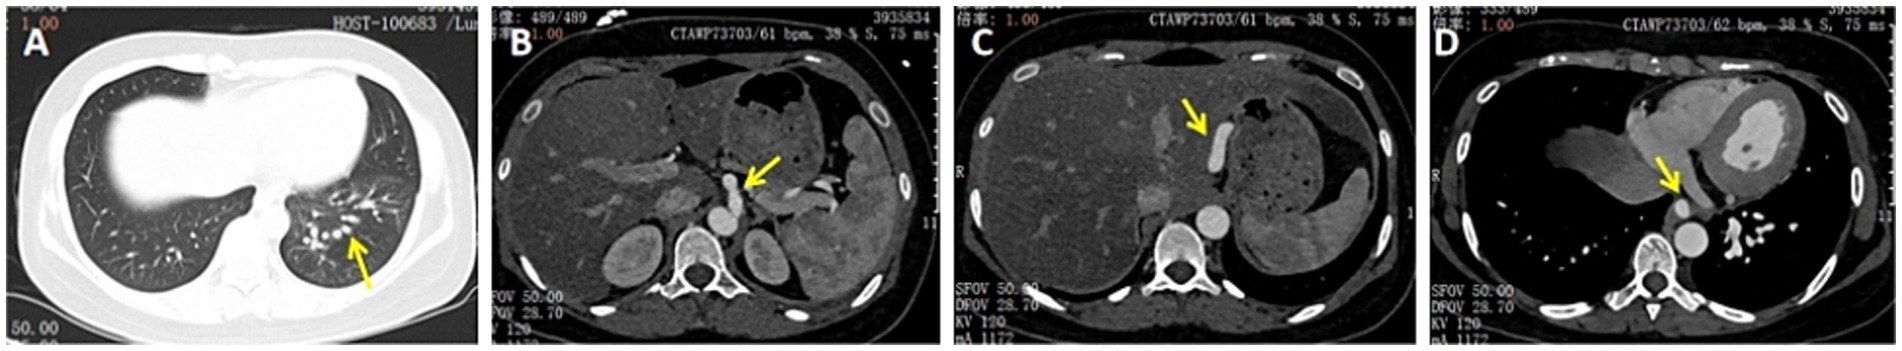

A 28-year-old female patient with a ten-year history of recurrent haemoptysis was transferred to our hospital. She had previously been diagnosed with bronchiectasis on multiple occasions at other medical facilities, despite undergoing treatment for both infection and haemostasis. She’s married with no children and no history of smoking. A physical examination revealed no abnormalities in her breathing or heart sounds. A comprehensive blood examination was conducted, encompassing various parameters including blood routine, liver and kidney function, and coagulation function. The results showed that the patient’s blood profile was normal. Computed tomography (CT) scan of the chest revealed thickening of the left lower pulmonary vein(Figure 1A). Subsequent computed tomography angiography (CTA) revealed an anomalous arterial branch arising from the celiac aorta,which originated at the T12-L1 level (Figures 1B–D). Angiographic examinations confirmed the presence of an anomalous artery originating from the celiac aorta. The diagnosis of anomalous celiac aorta supply to normal basal segments of the lung was thereby confirmed. Further diagnostic procedures were performed, including echocardiography. The results indicated a mean pulmonary artery pressure of 21 mmHg (normal range: 9–18 mmHg). There was no evidence of dilatation in the right atrium or right ventricle, nor of any observable enlargement of the pulmonary artery.

Figure 1. (A) CT of the chest showed thickening of the left lower pulmonary vein. (B–D) CTA showed bronchi in the blood supply area originating from the normal left lower pulmonary bronchi, and the pulmonary vein of the left lower hilar is thickened. The thick branch of the celiac aorta supplied part of the basal segments of the lung through the diaphragm (yellow arrow).